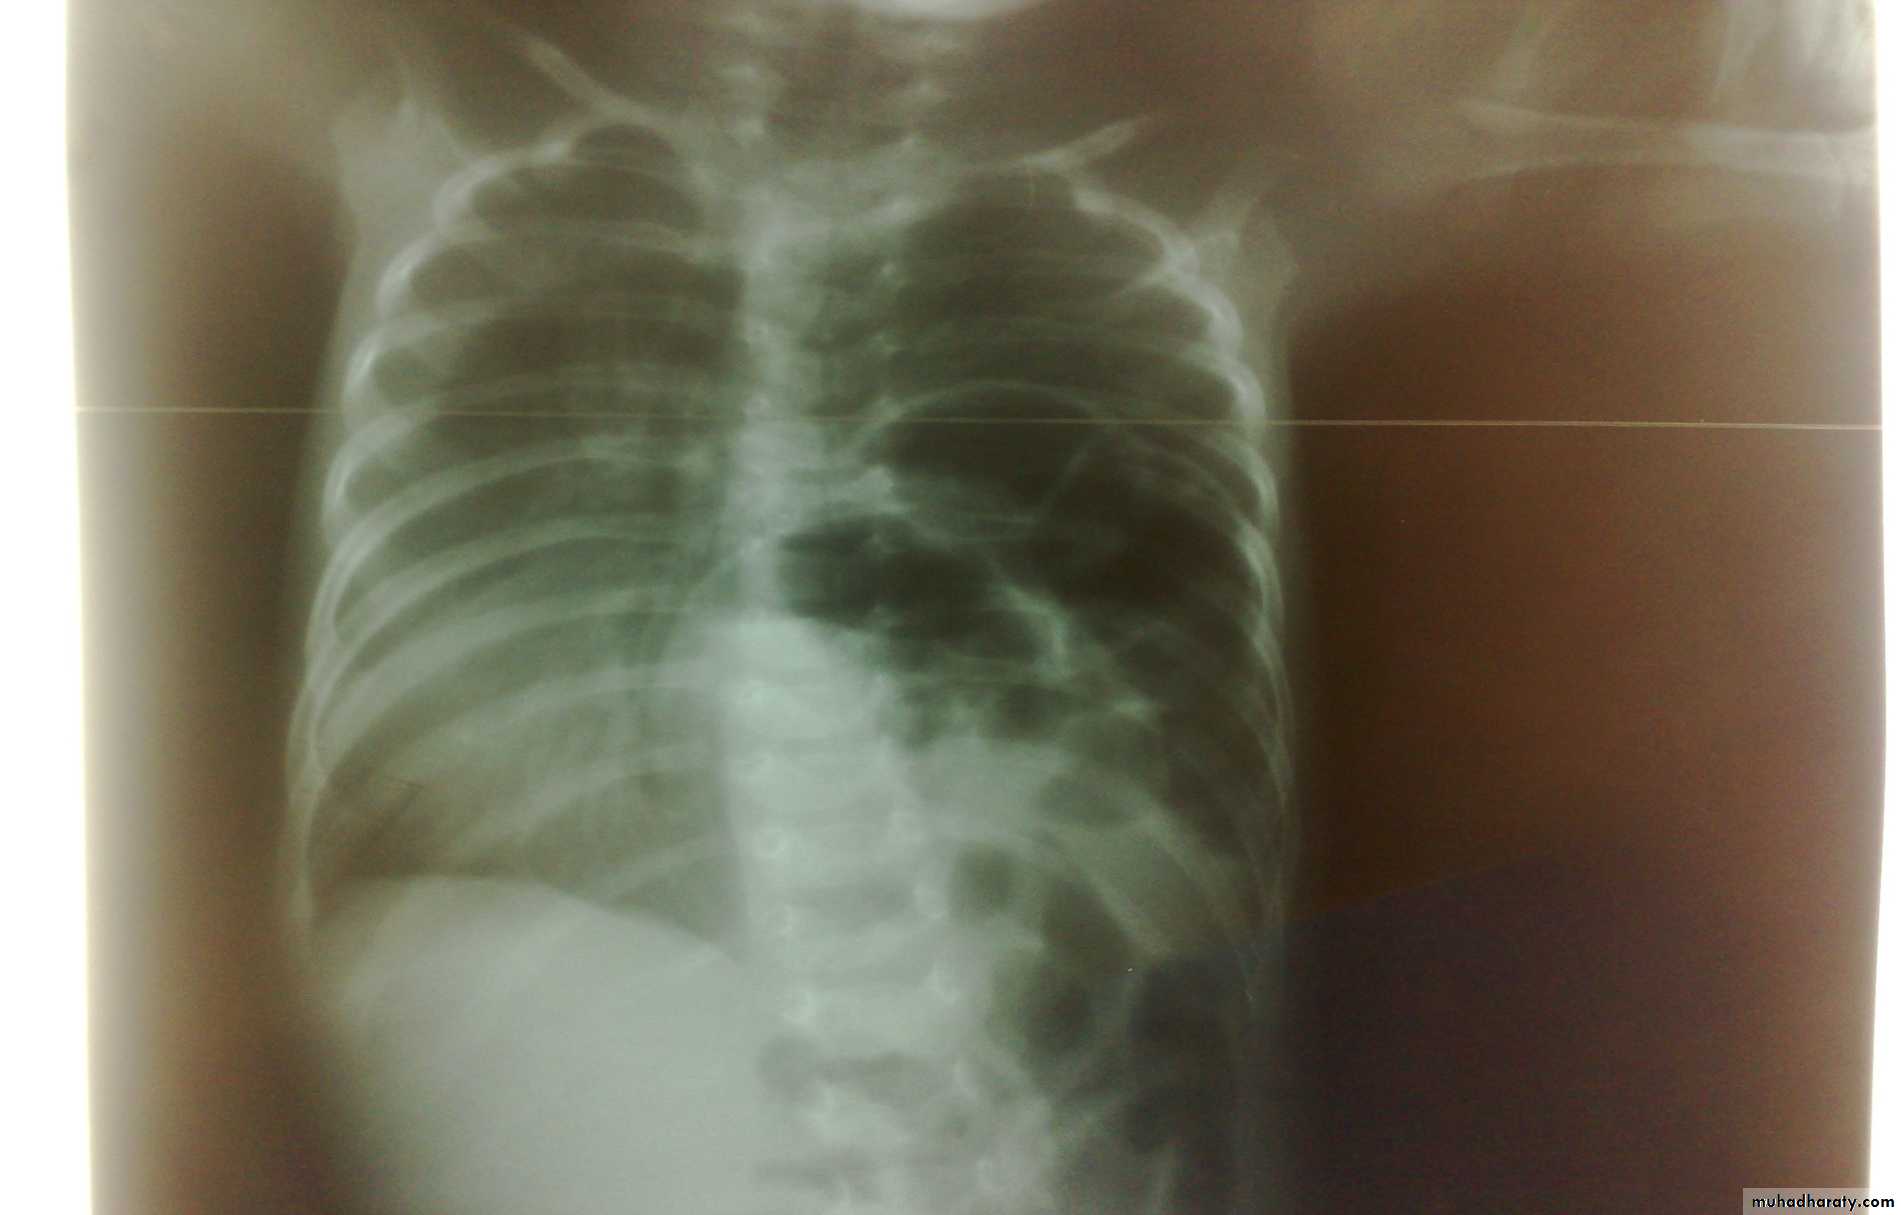

Scaphoid abdomen